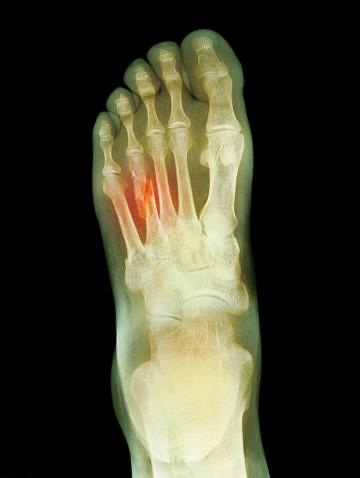

夾腳拖雖然輕鬆方便,卻因後跟未固定而穩定性不佳。行走時為防止脫落,腳趾會不自覺用力勾緊,長期恐養成不良步態。更危險的是騎機車穿拖鞋,一旦發生意外,腳部軟組織撕裂傷往往比單純骨折更棘手,重建難度極高。